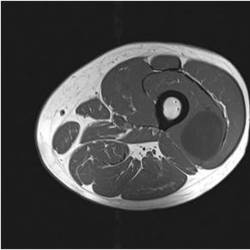

Gallery of Unlabled Radiographs from Lecture (Dr. French) - 2020

Click a thumbnail to enter the gallery display. Click the file name link at the bottom left of the gallery display to view the image at high resolution.